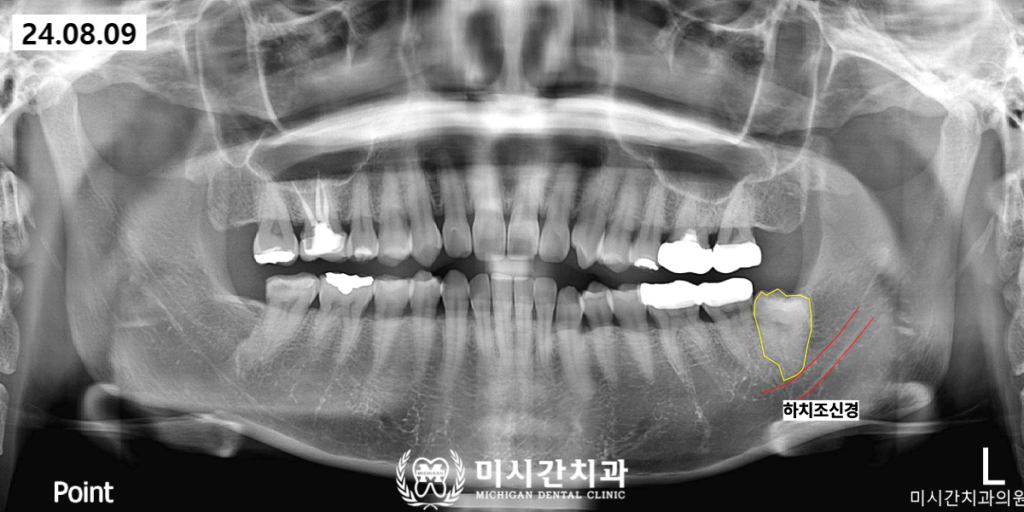

미시간치과에서는 최근 사랑니 부위의

반복적인 붓기와 통증으로 내원하신

환자분의 발치 사례를 성공적으로 마무리하였습니다.

해당 환자분은 사랑니가 잇몸 밖으로

거의 보이지 않는 완전 매복 상태였으며

방사선 사진 촬영 결과 치아가 옆으로

누워 있는 수평 매복 형태를 띠고 있었습니다.

무엇보다 주의 깊게 살펴야 했던 부분은

사랑니 뿌리가 아래턱 신경관과

매우 밀접하게 맞닿아 있다는 점이었습니다.

아래턱에는 하치조신경이라는 중요한

신경 다발이 지나가는데 사랑니 발치 과정에서

이 신경에 무리한 자극이 가해지면

입술이나 턱 주변에 감각 이상이 생길 위험이 존재합니다.

본 기관에서는 이러한 위험 요소를

사전에 차단하기 위해 삼차원 디지털 장비를

활용한 정밀 진단을 실시하였습니다.

정밀 진단을 통해 사랑니의 입체적인 위치와

신경관과의 거리를 밀리미터 단위로

분석한 결과 신경 손상 없이

발치가 가능하다는 판단을 내렸습니다.